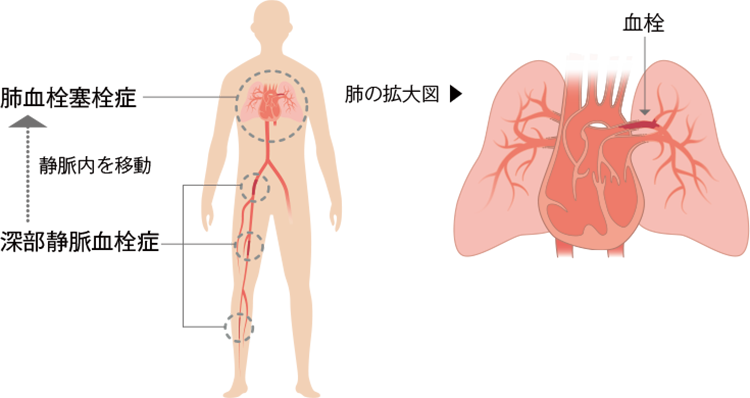

末梢血管疾患解説患者さまへイムス葛飾ハートセンタ。

川崎 静脈血栓塞栓症浅田内科・循環器内エコノミークラス症候群。

エコノミークラス症候群広島の調剤薬局 FINE PLUS まえだ薬局・プラス薬局 のブログ。

4 エコノミークラス症候群 肺血栓塞栓症 に関するQ&A - 4 エコノミークラス症候群 肺血栓塞栓症 に関するQ&A -災害時の対応について一般社団法人日本呼吸器学会。

川崎 静脈血栓塞栓症浅田内科・循環器内エコノミークラス症候群。

エコノミークラス症候群震災時に起こりやすい健康問題と予防法 1看護roo! カンゴルー。

深部静脈血栓症 DVT の病態と予防見て!わかる!病態生理と看護 花子のまとめノート。

4 エコノミークラス症候群 肺血栓塞栓症 に関するQ&A - 4 エコノミークラス症候群 肺血栓塞栓症 に関するQ&A -災害時の対応について一般社団法人日本呼吸器学会。

4 エコノミークラス症候群 肺血栓塞栓症 に関するQ&A - 4 エコノミークラス症候群 肺血栓塞栓症 に関するQ&A -災害時の対応について一般社団法人日本呼吸器学会。

エコノミークラス症候群 深部静脈血栓症 メカニズムのイラスト素材29374549- PIXTA。